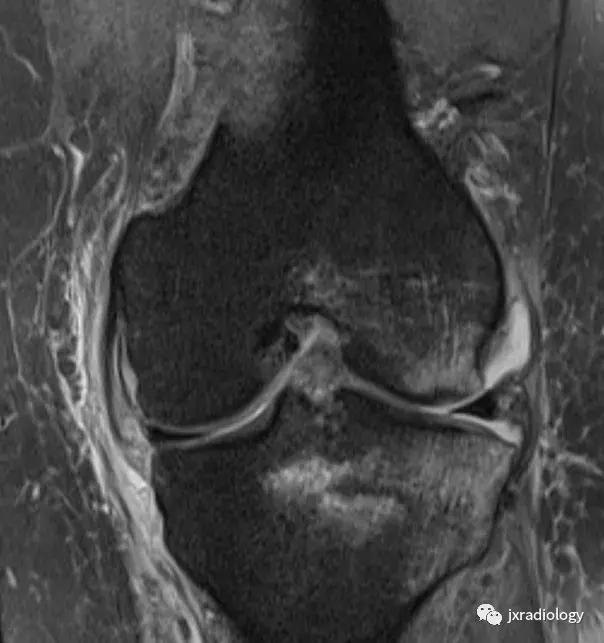

图2:骨性关节炎(OA):男,58岁,股骨内侧髁负重区有软骨缺损,伴有边缘小骨赘和继发性软骨下骨髓水肿。骨性关节炎通常不与创伤性病因分类,而是作为退行性病变分类(a:冠状T1-WI; b:冠状PDWI-FS; c:矢状PDWI-FS)。